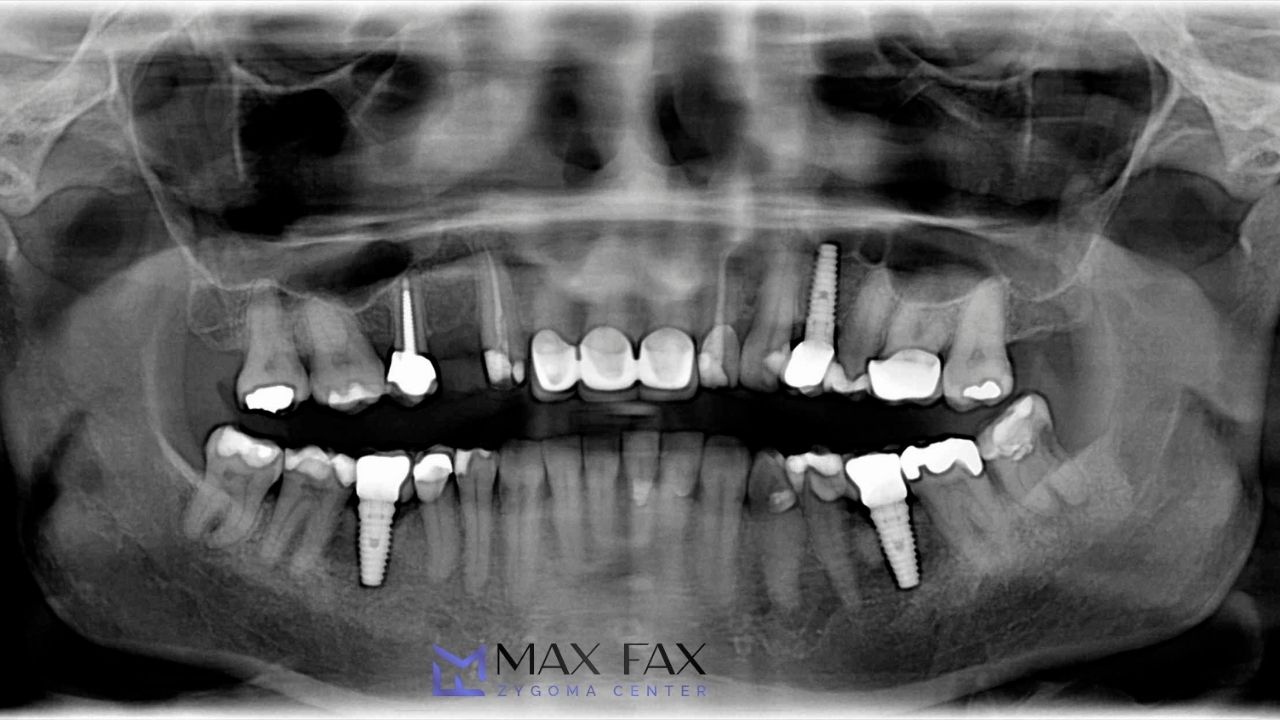

In its simplest form, the 3/2 rule for implant placement states that the visible crown portion of an implant-supported restoration should not exceed three times the height of the implant that is anchored in bone. In other words, for every 2 mm of implant emerging above bone, a maximum of 3 mm of prosthetic crown height is recommended. By respecting this proportion, the 3/2 rule for implant placement helps minimize excessive leverage and torque forces acting on the implant body, abutment, prosthetic screw, and surrounding bone tissue.

The 3/2 rule for implant placement is particularly relevant in situations where implant length is limited, such as when there is bone resorption in posterior maxilla cases or when anatomical structures like the sinus cavity restrict implant positioning. Maintaining proper proportions through the 3/2 rule for implant placement provides a biomechanical safety buffer that reduces overload on the supporting tissues.

During treatment planning, the 3/2 rule for implant placement is considered alongside factors such as bone volume, density, occlusion, facial profile, bite forces, and aesthetic expectations. Advanced imaging, including CBCT scans, allows surgeons like Prof. Dr. Celal Çandırlı to assess whether the 3/2 rule for implant placement can be achieved or whether bone augmentation, sinus lifting, or alternative implant selection is required.